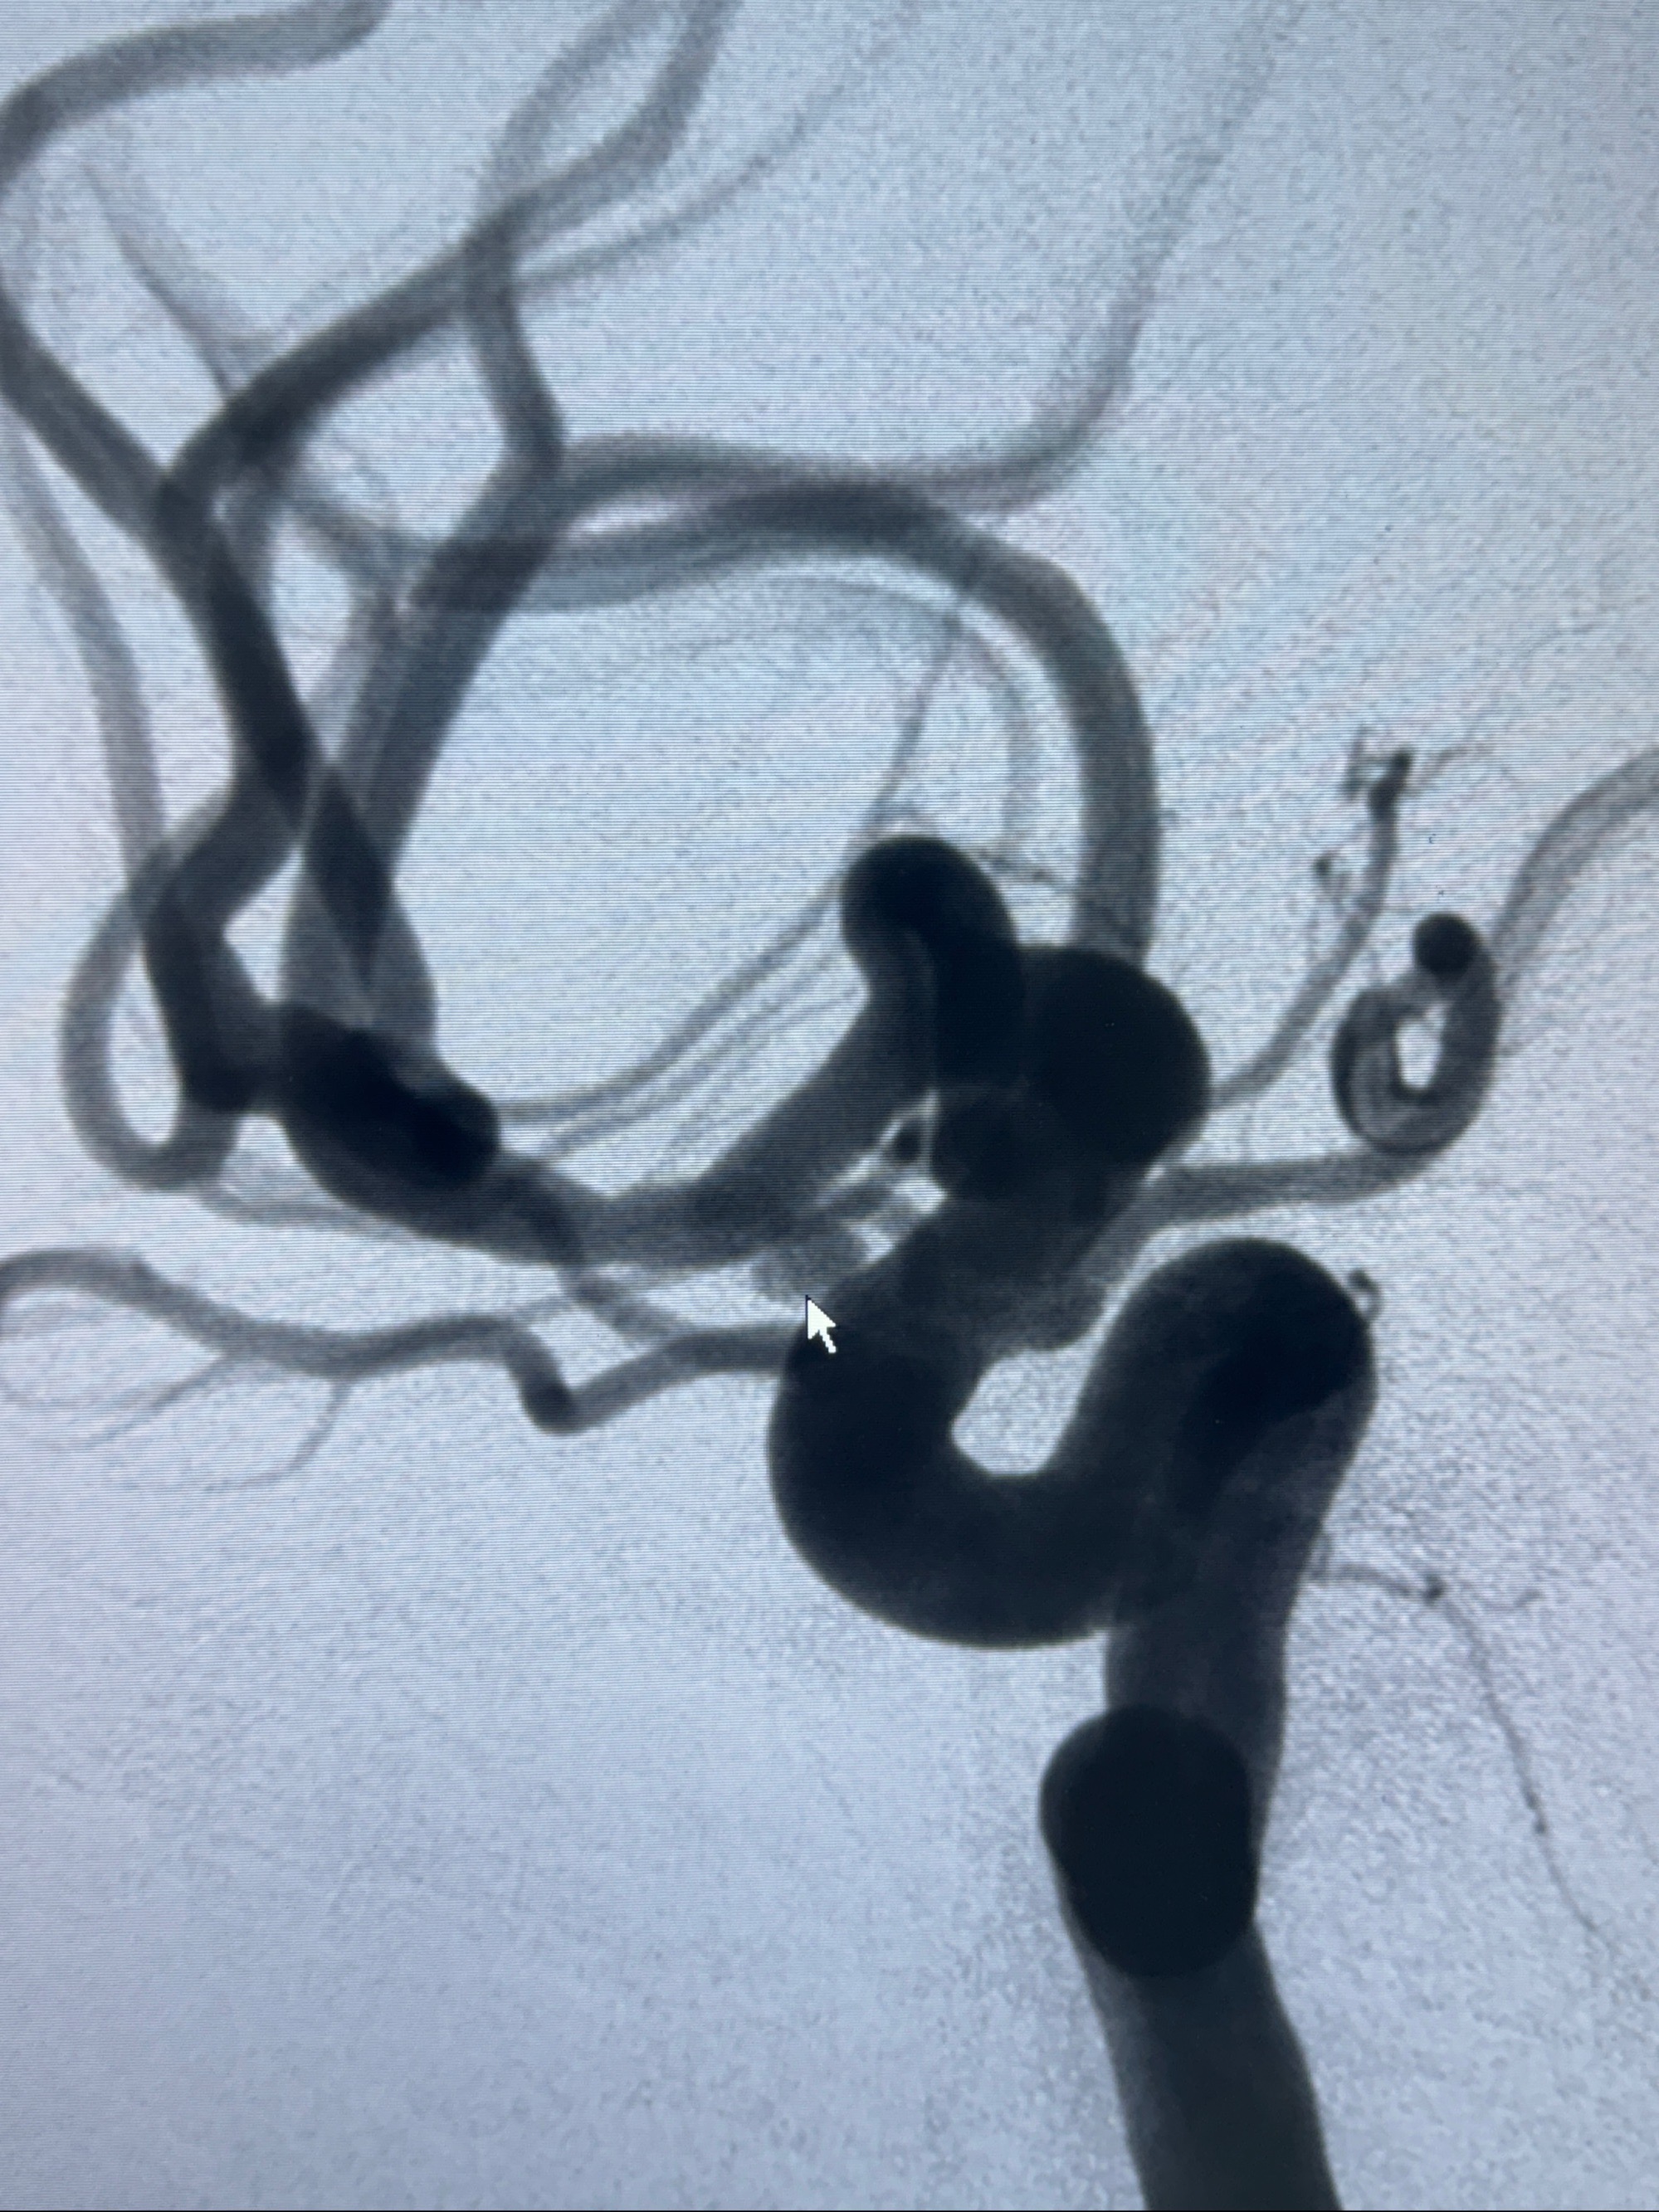

2023-11-24DSA:右侧大脑中动脉下干起始部动脉瘤,约2.3*2.5mm,形态规则

2023-12-04全麻下行支架辅助治疗

S-AB4-20mm

麻醉苏醒佳,遵嘱动作

术后即刻CT